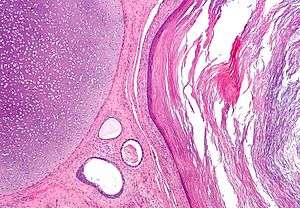

The surface ectoderm develops into: epidermis, hair, nails, lens of the eye, sebaceous glands, cornea, tooth enamel, the epithelium of the mouth and nose.